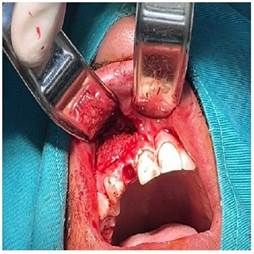

En el segundo tiempo quirúrgico se utilizó A - PRF (Advancet - platelet rich fibrin), se realizó una incisión Neumann modificada, levantamiento del colgajo mucoperiostico, se extrajo cuidadosamente la pieza 1.2, se realizó el curetaje de la cavidad quística retirando en su totalidad la membrana verificando que el hueso quede totalmente limpio (Figura 6a), posteriormente rellenamos la cavidad con el A-PRF y un injerto óseo compuesto por una membrana de colágeno hemostático bovino con hidroxiapatita porosa absorbible (Figura 6b). Se realizó la reposición del colgajo con 9 puntos de sutura simples discontinuos. Se le prescribió como medicación pre operatoria amoxicilina de 1 gr cada 12 horas por 7 días comenzando el día anterior a la intervención, se indicó medicación analgésica postoperatoria inmediata con ketorolaco sublingual 30 mg y posteriormente ketoprofeno 100 mg cada 12 horas por 3 días.

Figura 6b Cavidad rellena con A-PRF en conjunto con el injerto óseo de membrana de colágeno hemostático bovino e hidroxiapatita porosa reabsorbible.